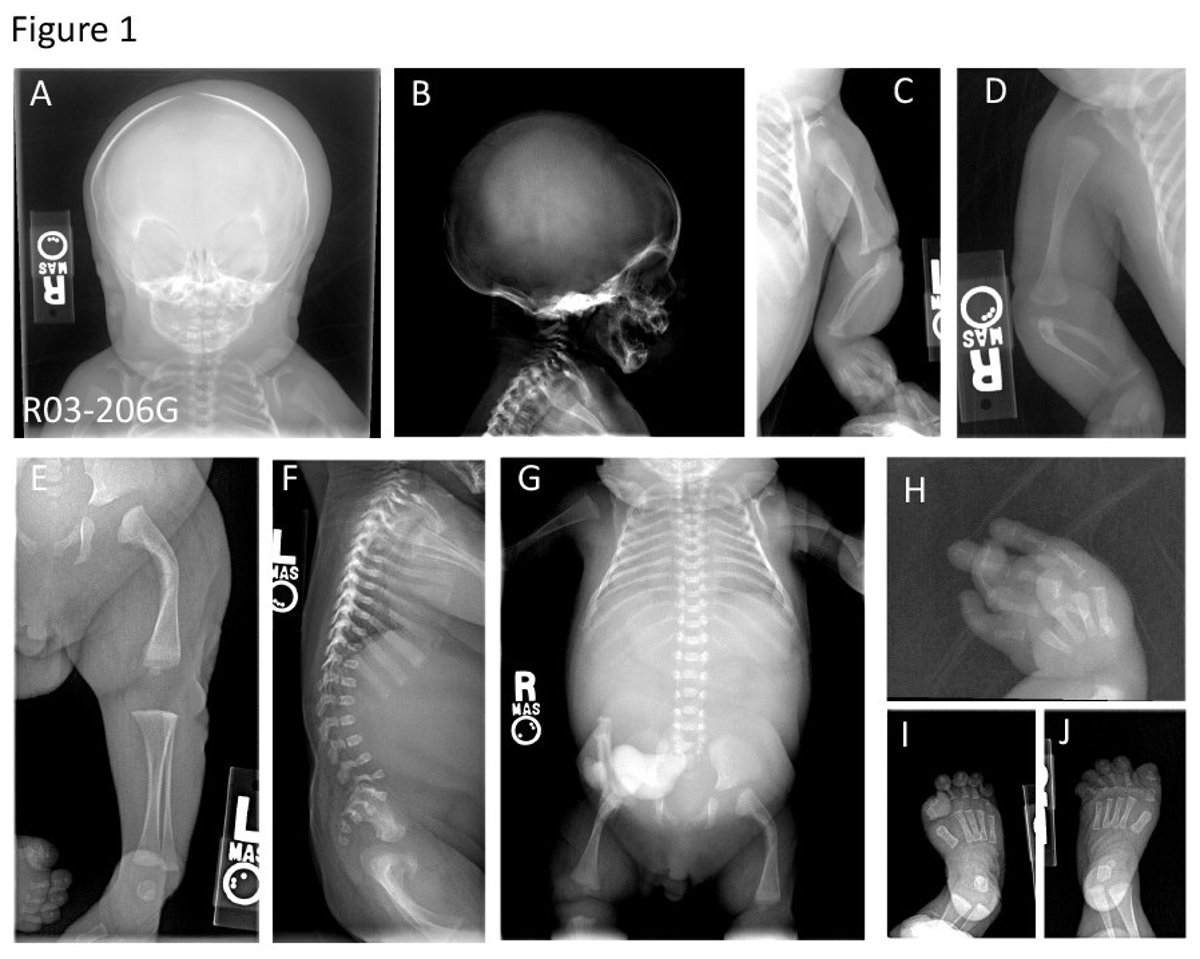

Esta enfermedad consiste en una fragilidad ósea extrema con falta de mineralización y deformación esquelética asociada con dislocación en articulaciones y cardiopatías, así como una deficiencia pulmonar que provoca letalidad perinatal --en el momento del nacimiento--.